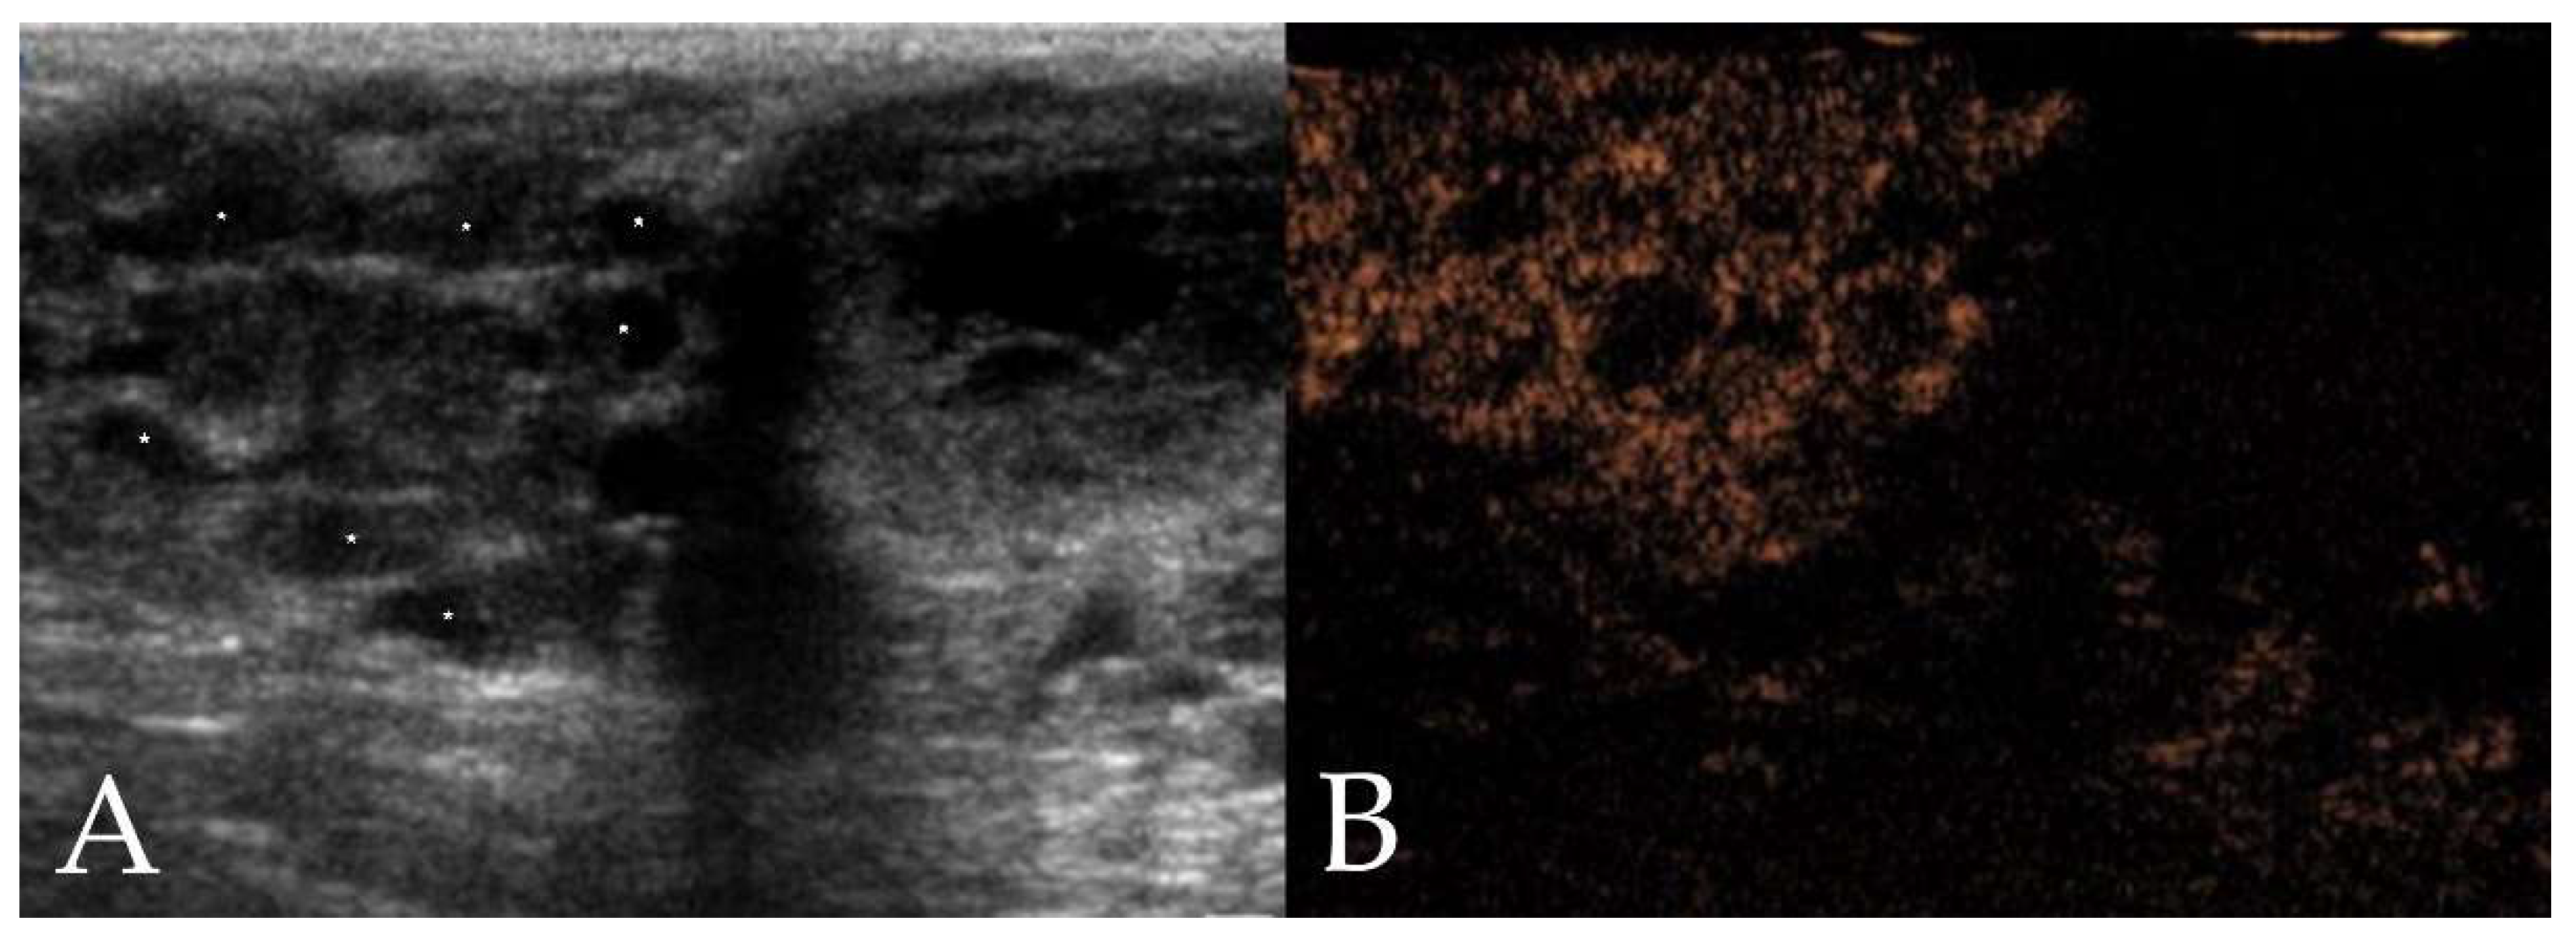

3.2.1. B-Mode Ultrasound

3.2.2. Qualitative CEUS